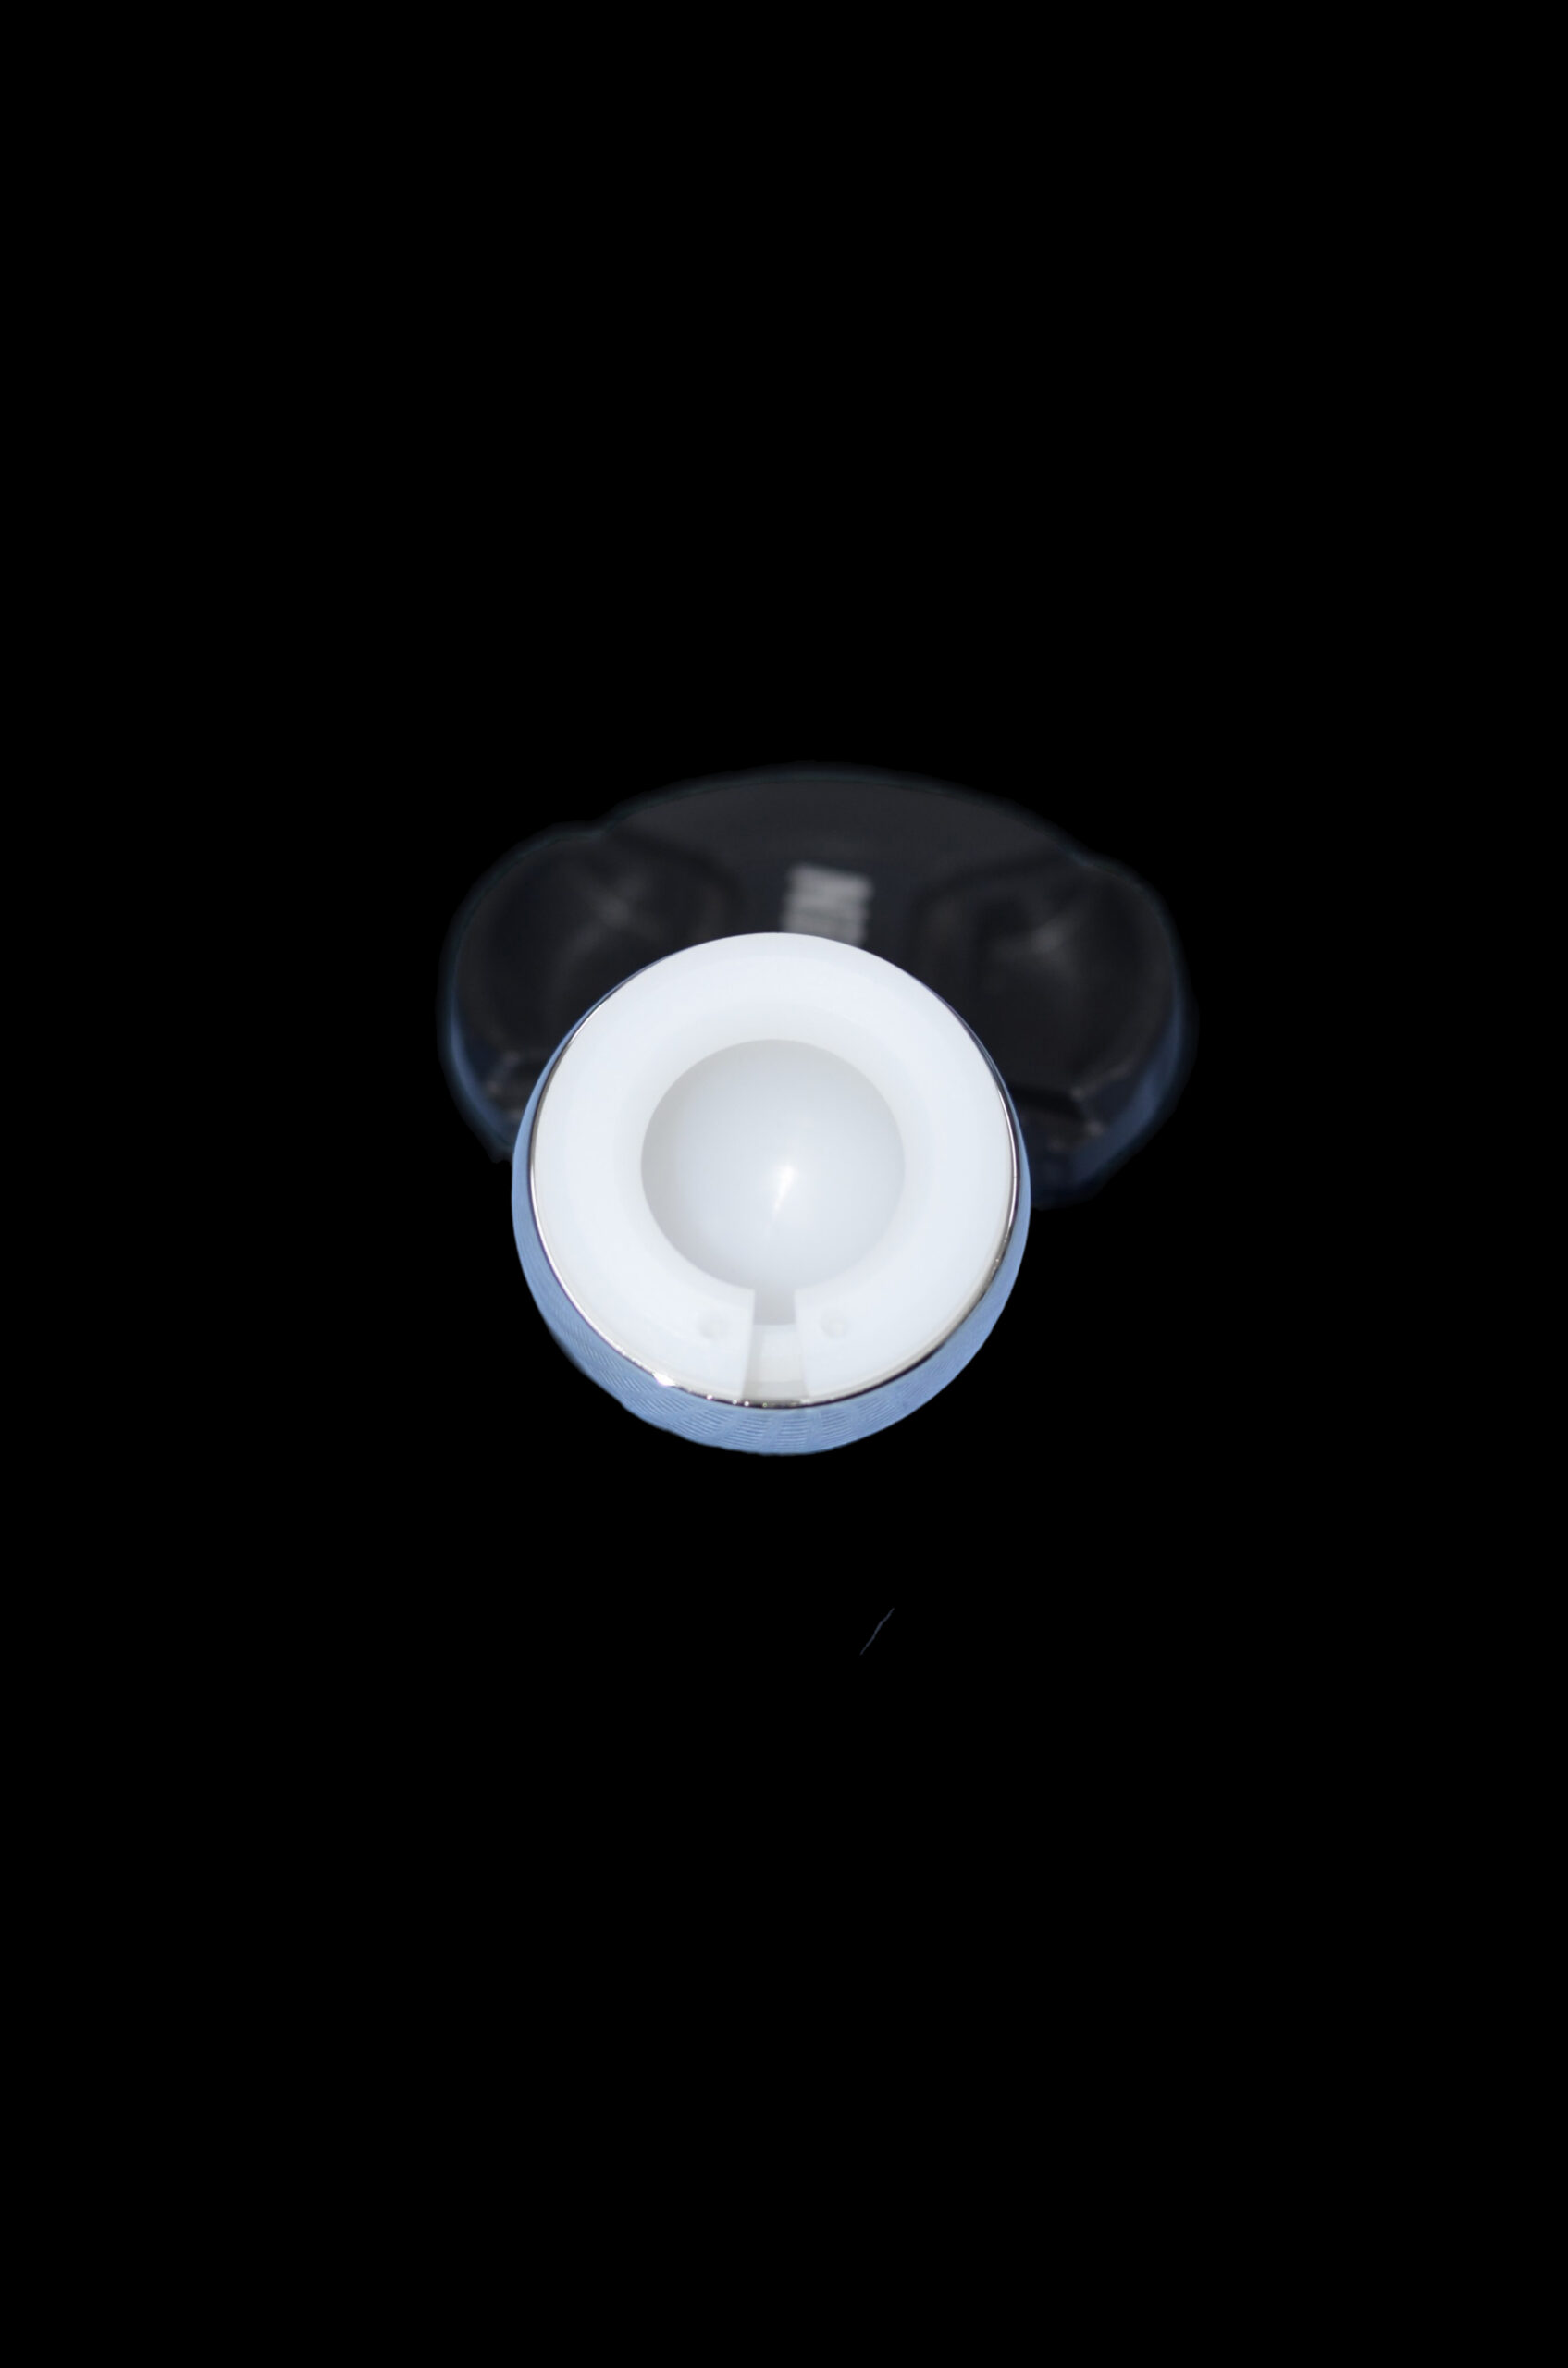

Bipolar Hip Prosthesis is designed to provide effective treatment for hip fractures and degenerative conditions, featuring a dual articulation system that reduces wear and enhances mobility. With precision engineering and biocompatible materials, it ensures patient comfort, stability, and long-term performance—reflecting Orthomed‑E’s dedication to advanced orthopedic solutions.